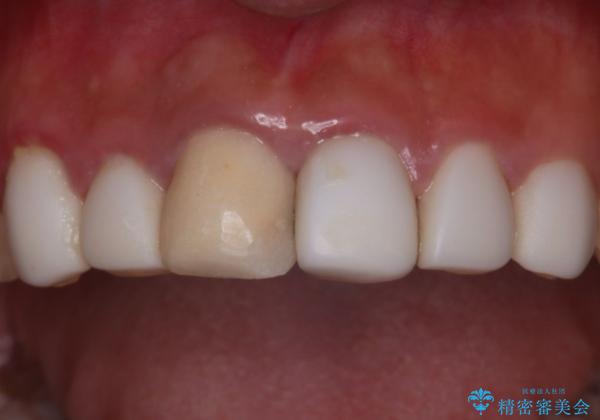

清掃性も上がったおかげで、歯肉の状態も良好に保てています。

色の調和もとれたので非常に満足いただけました。